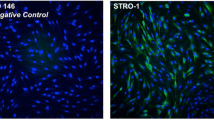

Flow cytometric analysis

At the end of the second passage, most cells showed positive expression of the mesenchymal stem cell marker (CD73) and negative expression of the hematopoietic cell marker (CD45). The percentage of positive cells was 99.9% for CD73 and 32.8% for CD45 (Fig. 3).